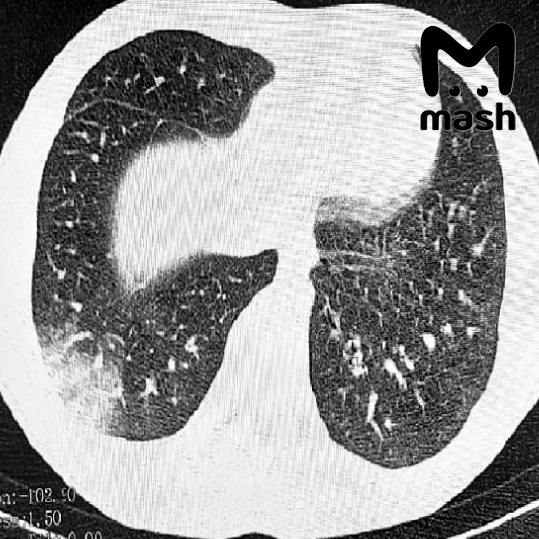

33-летняя девушка обратилась к врачам с охрипшим голосом. После обследований ей диагностировали плоскоклеточный рак гортани. По данным медиков, причина — пять лет курения дуделок. Такой же случай у ростовчанина — он три года выкуривал по десять стиков каждый день и заработал сильную осиплость голоса. Обследование показало большую опухоль в горле.

Вейпы и всевозможные дуделки опаснее классических сигарет потому, что кажутся безобидными. На самом деле в них содержится глицерин, вызывающий пневмонию и специфический синдром EVALI, и нагретые химикаты и тяжёлые металлы. Ароматизаторы усиливают вкусовую зависимость и усиливают токсический эффект.